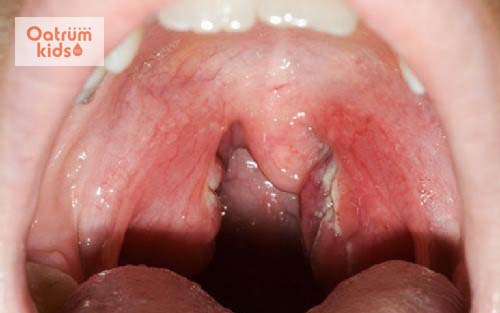

Vòm họng trẻ có đốm trắng có phải dấu hiệu của căn bệnh nguy hiểm?

Vùng hầu họng là một trong những vùng nhạy cảm khiến trẻ dễ bị nhiễm bệnh nhất. Chính vì thế khi nhận thấy vòm họng trẻ có đốm trắng mẹ thường rất lo lắng, bởi đây có thể là dấu hiệu của một bệnh nguy hiểm nào đó.